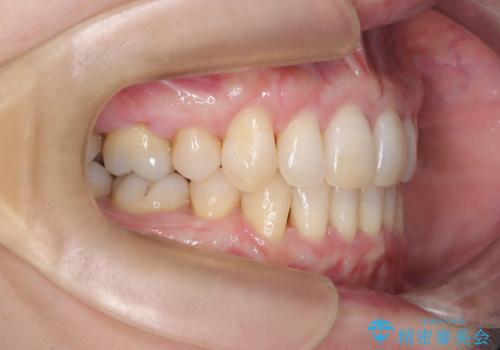

- 前歯の凸凹と前突感を改善するため、上下左右の4番を抜歯し、空いたスペースを利用して前歯を後方へ下げる審美ワイヤー矯正を計画しました。抜歯後は透明で目立ちにくい審美ブラケットを装着し、ワイヤーを用いて徐々に歯列を整えます。毎月1回の調整を通じて歯並びの変化を確認しながら、丁寧に矯正を進め、約2年で理想的な歯列と噛み合わせを完成させることを目指します。

前歯が前に出ていることや歯並びの凸凹が気になるという主訴でした。十分なスペースを確保するため上下左右の第一小臼歯(4番)を抜歯し、そこに前歯を移動させて整列を行いました。矯正装置には目立ちにくい透明なブラケットを選択し、見た目のストレスを軽減。矯正期間中は定期的な通院でワイヤーを微調整し、無理なく確実に歯を動かしました。治療後は前歯が自然な位置に下がり、口元の突出感が解消されるとともに、美しく整った口元に仕上がり、患者様にも大変喜んでいただけました。